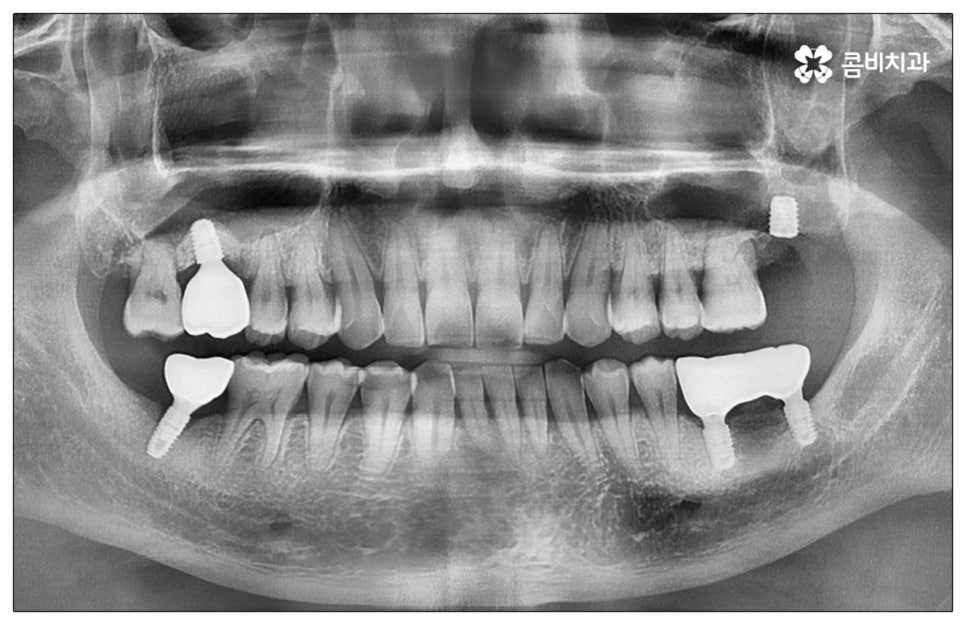

예전에는 이런 상황에서 틀니를 많이 이용하였으나 저작력 회복이 본래 자신의 치아 대비 20~30% 정도 밖에 되지 않고 잦은 탈락 위험 및 이물감, 잇몸을 눌러 장기적으로 잇몸뼈가 내려앉을 수 있다는 점 등 여러 가지 불편함이 있어 요즘은 임플란트 시술을 선호하시는 분들이 더 많아지고 있어요. 임플란트란 인체에 무해하며 잇몸뼈와 잘 결합하는 인공 치근을 잇몸뼈에 직접 식립하고 그 위로 기둥이 되는 중간 지대주와 치아 머리가 되는 크라운 보철물을 연결하여 인공 치아를 만들어 주는 시술을 말하는데, 자연 치아의 80% 정도 저작력 회복이 가능하기 때문에 식사를 할 때 음식을 크게 가리지 않아도 된다는 점 그리고 심미적으로 봤을 때 주변 치아와 자연스럽게 어우러진다는 점 때문에 각광을 받고 있습니다. 게다가 건강 보험 가입자이면서 만 65세 이상 부분 무치악 환자라면 평생 임플란트 2개까지 보험 적용을 받아 비용 부담을 줄일 수 있기 때문에 더욱 더 수요가 늘어나 이제는 치아 상실에 대체하는 대표적인 방법으로 임플란트 시술이 꼽히고 있는데요.

많이 대중화 되었다고 해도 임플란트 수술 자체가 술자의 숙련도에 크게 영향을 받는 복잡하고 고난도의 진료인 것은 틀림이 없기 때문에 담당 의료진이 해당 분야 임상 경험이 풍부한지, 뛰어난 기술력과 노하우를 가지고 있는지 꼼꼼하게 체크해 보실 필요가 있어요. 특히 노년층의 경우 당뇨, 고혈압 등 만성 질환을 앓고 있는 경우가 많아 혹시 상시 복용하고 있는 약이 있는지, 현재 환자 개개인의 상태는 어떤지, 사전 처치가 필요한 부분은 없는지 등등 수술 조건을 좀 더 까다롭게 평가한 후 환자분들과 이에 대해 충분히 상담하고 맞춤형 치료 계획을 세워 진행해야 하며 이를 위해 3D CT 와 같은 디지털 검진 장비를 통해 구강 내부 구조를 면밀하게 살피고 방대한 임상 데이터를 축적한 정품 임플란트 재료를 이용하여 연령이나 회복 정도를 살펴보면서 체력적 부담을 줄이는 방향으로 무리하지 않게 식립하는 것이 무엇보다 중요하다고 할 수 있습니다.

이때 추가 수술은 비급여 항목으로 건강보험임플란트 대상에서 제외되니 이에 대해서도 꼼꼼하게 살펴보시고 정밀 검진 후 담당 의료진과 자신의 상황에 대해서 충분하게 상담해 보시길 권유드리고 있습니다. 추가 수술의 대표적인 예로는 뼈이식 수술이 있는데요. 이것은 임플란트를 식립할 때 바탕이 되는 잇몸뼈의 높이나 폭, 밀도 등이 부족하다면 먼저 이를 보충해 주고 나서 임플란트를 심어주는 과정을 의미하며 같은 이유로 식립 성공률이나 장기적인 안정성을 높이기 위해 꼭 필요한 사전 처치, 즉 상악동 거상술 및 치주 질환 관련 수술 등을 먼저 해야 한다면 이 역시 추가 수술의 범주로 들어가니 자신의 상황에 대해서 상세하게 알아보실 필요가 있어요.

임플란트 치아는 관리를 철저하게 해 주면 거의 반영구적으로 쓸 수 있으니 환자분들의 입장에서 구강 위생을 깨끗하게 유지시키고 또한 정기적으로 치과에 내원하셔서 스케일링 및 검진 진료를 받으시면 도움이 될 거예요. 임플란트는 자연 치아와 주변 조직이 다르기 때문에 특히 잇몸 질환을 주의해야 하며 수직력에는 강하지만 수평력에는 약한 특징을 가지니 혹시라도 이갈이 등의 습관을 가지고 있다면 이를 고칠 수 있도록 노력하시는 것이 임플란트 치아를 보다 오랜 기간 건강하게 사용하실 수 있는 지름길이라고 할 수 있습니다.